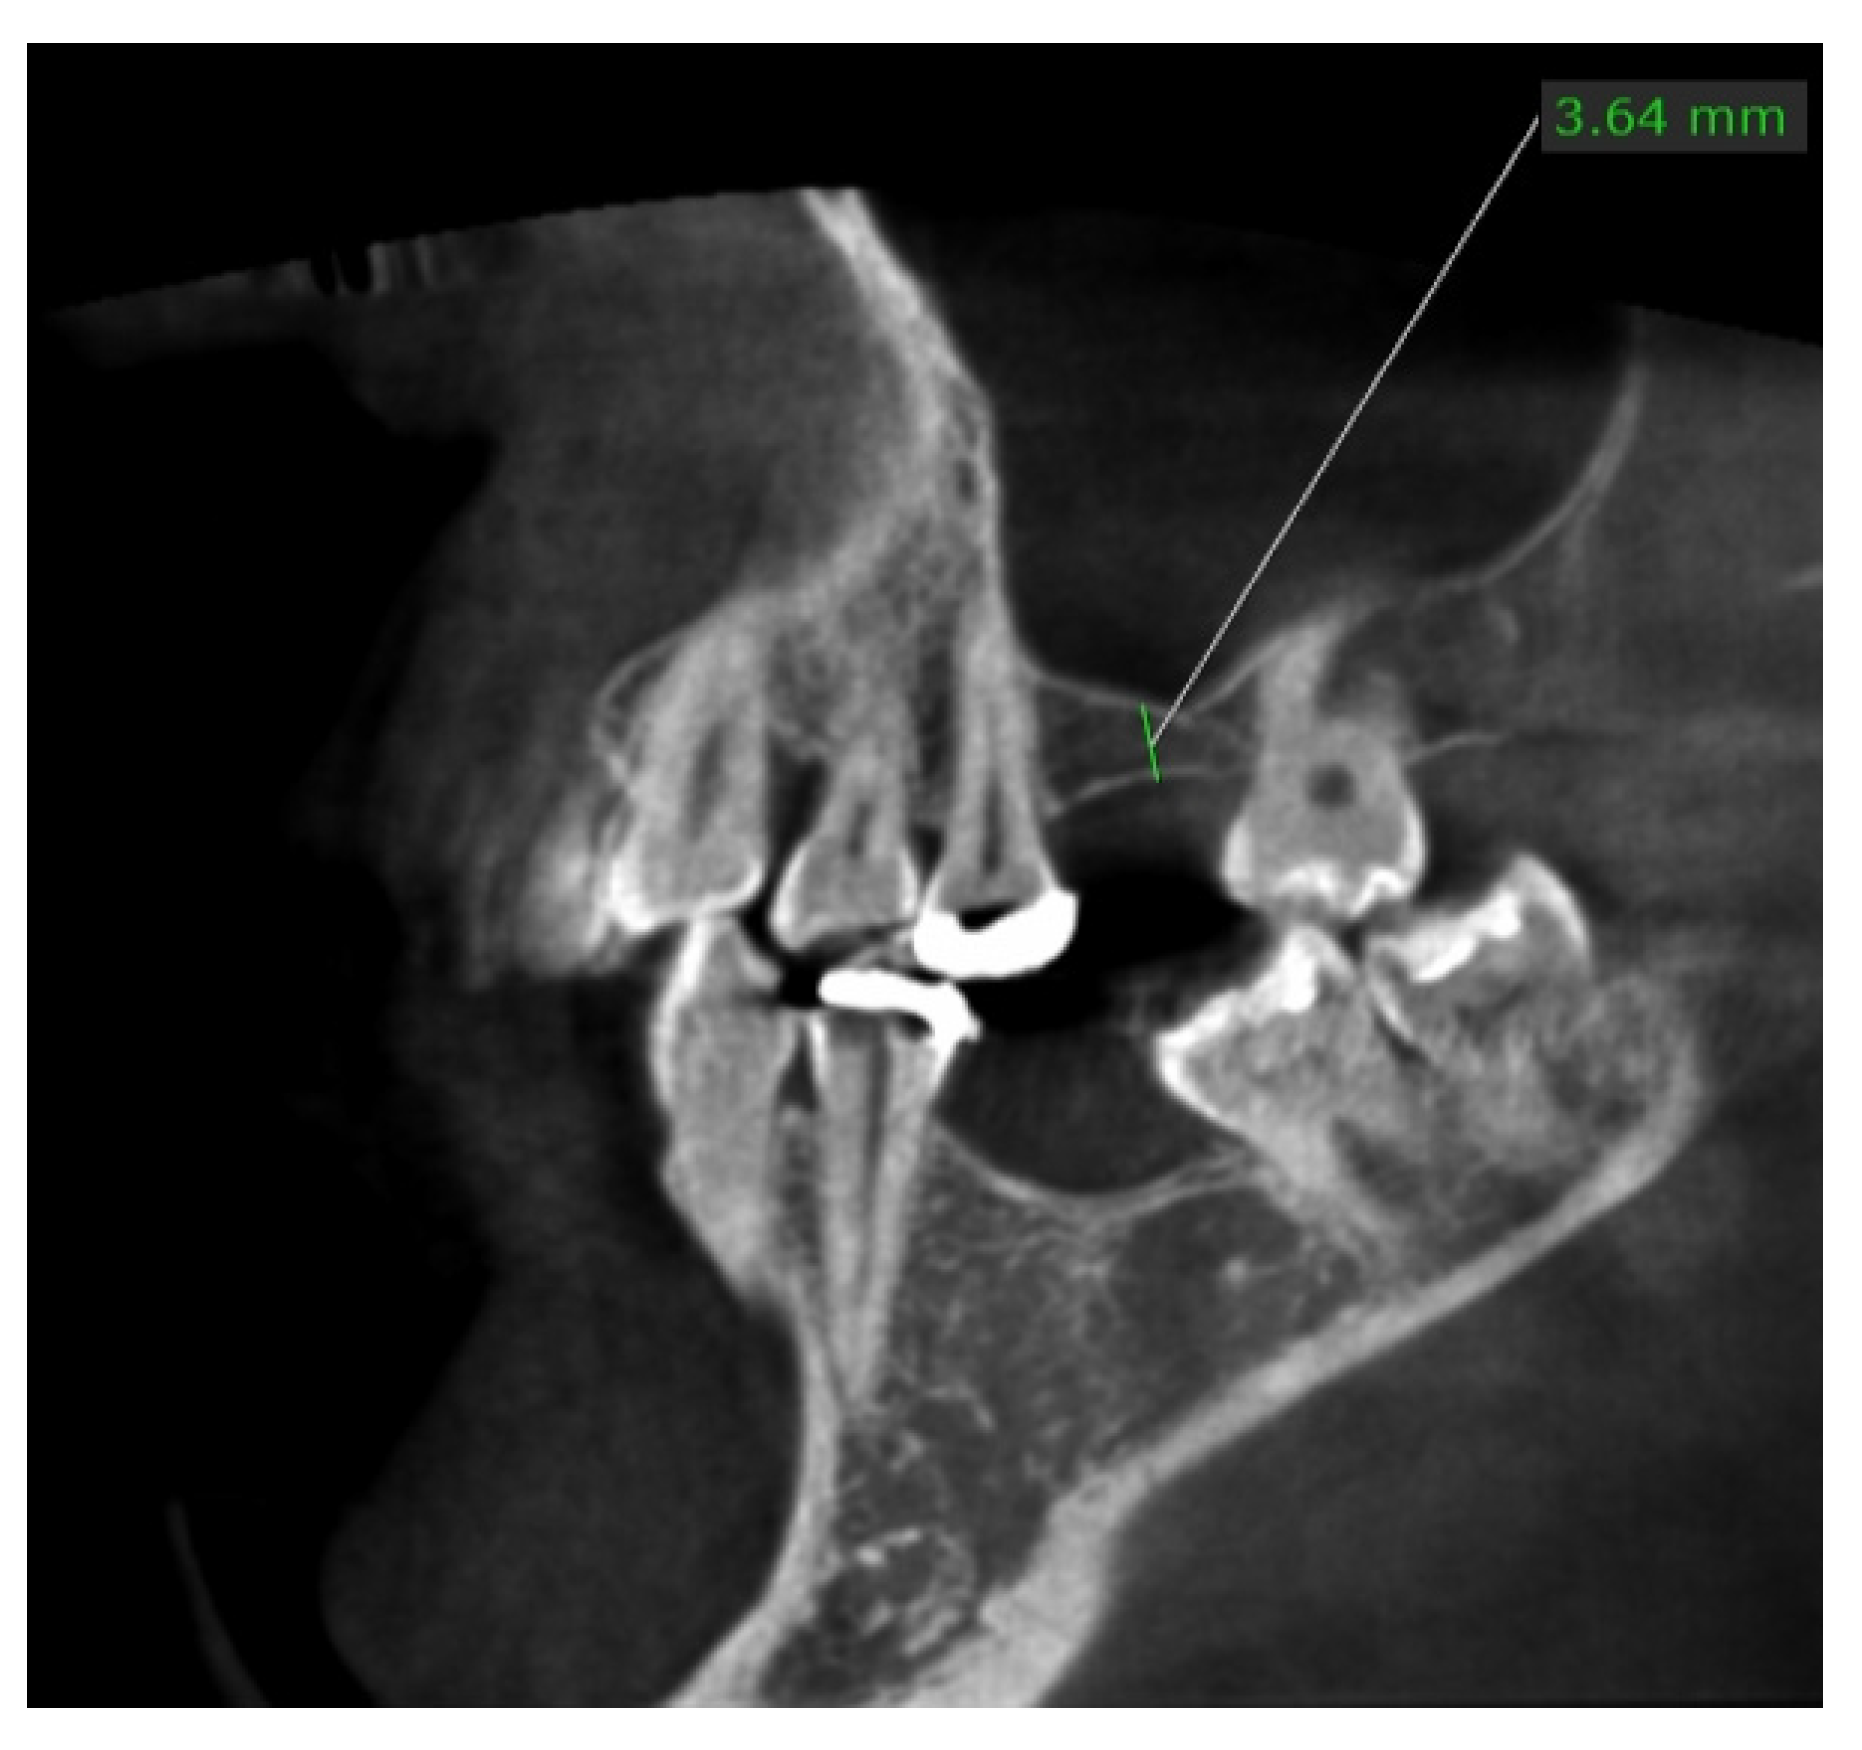

Case Presented with Histomorphologic Evaluation